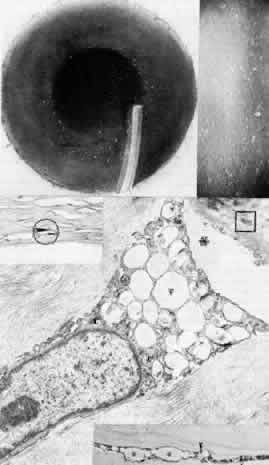

Fig. 9. Granular corneal dystrophy. Top left. Discrete, large opacities predominantly affect the central stroma. Top right. Retroillumination emphasizes the optical clarity of intervening stroma between granular opacities. Middle left. Light microscopy of hyaline deposits is accentuated with Masson trichrome stain (× 250). Right. Transmission electron micrograph shows relatively normal epithelium (E) and basement membrane (arrowheads) anterior to large electron-dense deposits (*) within Bowman's layer and stroma (× 4,500). Bottom left. Higher magnification transmission electron micrograph of granular deposits shows characteristic rod-shaped paracrystalline structure ( × 50,000). (Top right, Slit lamp photograph courtesy of Lawrence Hirst, MD)

Jones and Zimmerman99 noted the opacities to consist of areas of hyaline degeneration in which stromal fibers appeared “granular.” Histologically, the deposits stain red with Masson trichrome stain and are less PAS-positive and less birefringent than the normal stroma. Numerous argyrophilic fibers are seen on Wilder's reticulin stain. Using histochemical techniques, Garner100 concluded that the deposits consisted mainly of noncollagenous protein containing tryptophan, arginine, tyramine, and sulfur-containing amino acids, and he postulated that the abnormal proteins originated from the epithelium, keratocytes, and extracorneal sources. Rodrigues and co-workers101 found immunofluorescent evidence of microfibrillar protein, a poorly characterized glycoprotein, as well as a Luxol fast blue-staining phospholipid. Johnson and co-workers suggest an epithelial origin of the deposits based on light and electron microscopic studies of corneas with recurrent granular dystrophy.102 On transmission electron microscopy, the deposits appear as extracellular, rod-shaped, electron-dense paracrystalline structures with faintly visible periodicity. Keratocytes, endothelium, and Descemet's membrane appear unaffected.103